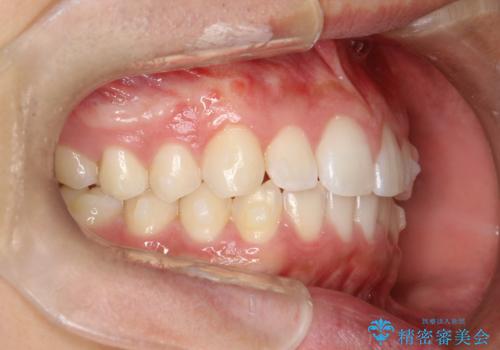

前歯の隙間がきになる インビザラインですきっ歯の治療

- 上の前歯の隙間を主訴に来院されました。

正中に隙間があり、かみ合わせが深い過蓋咬合という状態でした。

インビザラインにて矯正治療を行いました。

しっかり使っていただけたので、スムーズに治療を終了することができました。